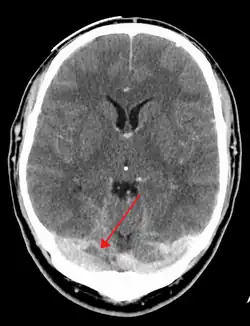

CT venogram showing a filling defect in the sagittal sinus (black arrow)

There are various neuroimaging investigations that may detect cerebral sinus thrombosis. Cerebral edema and venous infarction may be apparent on any modality, but for the detection of the thrombus itself, the most commonly used tests are computed tomography (CT) and magnetic resonance imaging (MRI), both using various types of radiocontrast to perform a venogram and visualise the veins around the brain.[3]

Computed tomography, with radiocontrast in the venous phase (CT venography or CTV), has a detection rate that in some regards exceeds that of MRI. The test involves injection into a vein (usually in the arm) of a radioopaque substance, and time is allowed for the bloodstream to carry it to the cerebral veins – at which point the scan is performed. It has a sensitivity of 75–100% (it detects 75–100% of all clots present), and a specificity of 81–100% (it would be incorrectly positive in 0–19%). In the first two weeks, the "empty delta sign" may be observed (in later stages, this sign may disappear).[11] The empty delta sign is characterized by enhancement of the dural wall without intra-sinus enhancement.[6]